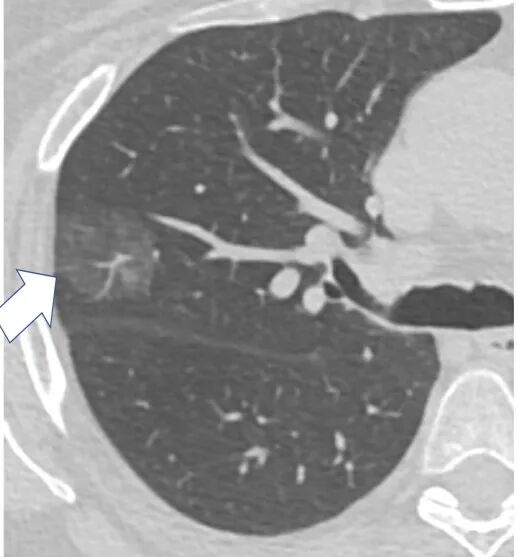

3.2肺结节密度

①一般来说,亚实性结节(包括纯磨玻璃结节和混合磨玻璃结节)的恶性概率高于实性结节;

②混合磨玻璃结节的恶性概率高于纯磨玻璃结节。